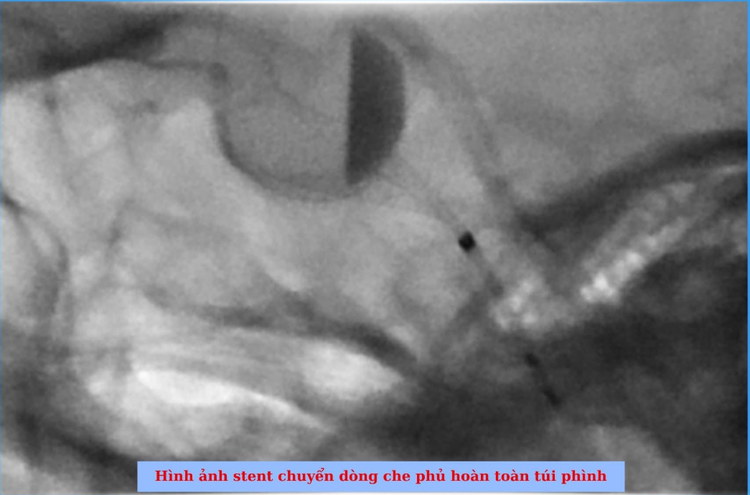

Sau khi hội chẩn kỹ lưỡng, đội ngũ y bác sĩ quyết định áp dụng phương pháp đặt stent chuyển dòng. Đây được xác định là lựa chọn phù hợp nhất cho trường hợp của bệnh nhân, vừa đảm bảo hiệu quả điều trị lâu dài, vừa hạn chế tối đa sự xâm lấn.

Ca can thiệp diễn ra trong vòng 1 giờ đồng hồ và kết thúc thành công. Túi phình đã được che phủ hoàn toàn bởi stent chuyển dòng. Đặc biệt, trong suốt quá trình can thiệp, bệnh nhân luôn giữ được trạng thái tỉnh táo và không xuất hiện bất kỳ biến chứng nào.